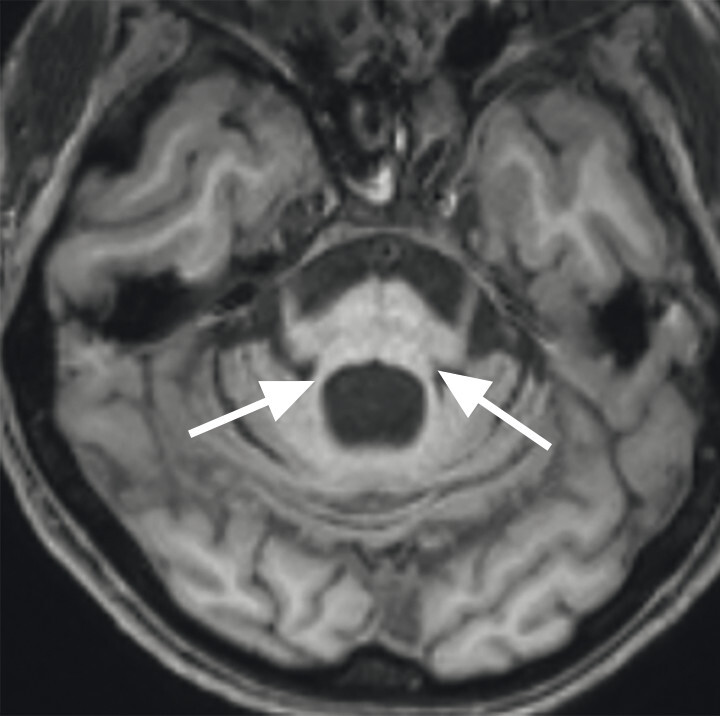

Abb. 69.7 Parkinson-Syndrome: Differenzialdiagnose Multisystematrophie vom zerebellären Prädominanztyp.

67-jährige Patientin mit über Jahre progredienter Verschlechterung des Gleichgewichts, Schluckstörungen und Sprechstörungen. In der T1w 3-D-Sequenz zeigt sich eine ausgeprägte Atrophie des Pons (a, Pfeil), der mittleren Kleinhirnstiele (b, Pfeile) und des Kleinhirns. Diese Veränderungen werden durch die Ganzhirnvolumetrie bestätigt (c): Anomale Regionen der grauen Substanz (mindestens 2 Standardabweichungen unter dem vergleichbaren Volumen des gesunden alters- und geschlechtsgematchten Normkollektivs) sind blau überlagert. Anomale Liquorvolumina (mindestens 2 Standardabweichungen über dem vergleichbaren Volumen des gesunden alters- und geschlechtsgematchten Normkollektivs) sind als rote bis gelbe Überlagerungen auf das individuelle Patientengehirn projiziert. MRT-morphologisch lässt sich somit die Verdachtsdiagnose Multisystematrophie vom zerebellären Prädominanztyp bestätigen.

a Sagittale T1w 3-D-MRT-Sequenz.

b Axiale T1w 3-D-MRT-Sequenz.

c Voxel- und regionenbasierte Analyse.